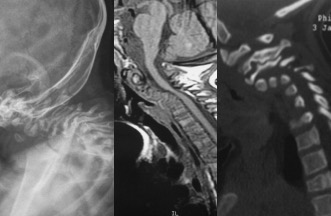

- Figura 8. Radiografías cervical AP y Lateral

- Figura 2. Tomografia Axial. Inestabilidad Atlanto - Axial

- Figura 3. Resonancia Magnética sin evidencia de lesión medular

- Figura 4. Tomografía reconstrucción 2D. Muesta inestabilidad C1-C2. Hipoplasia de Odontoides

- Figura 1. Radiografias preoperatorias AP y Laterales